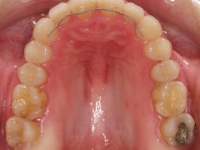

Premolar mandibular incluido + fenestración

Radiografía de final de tratamiento